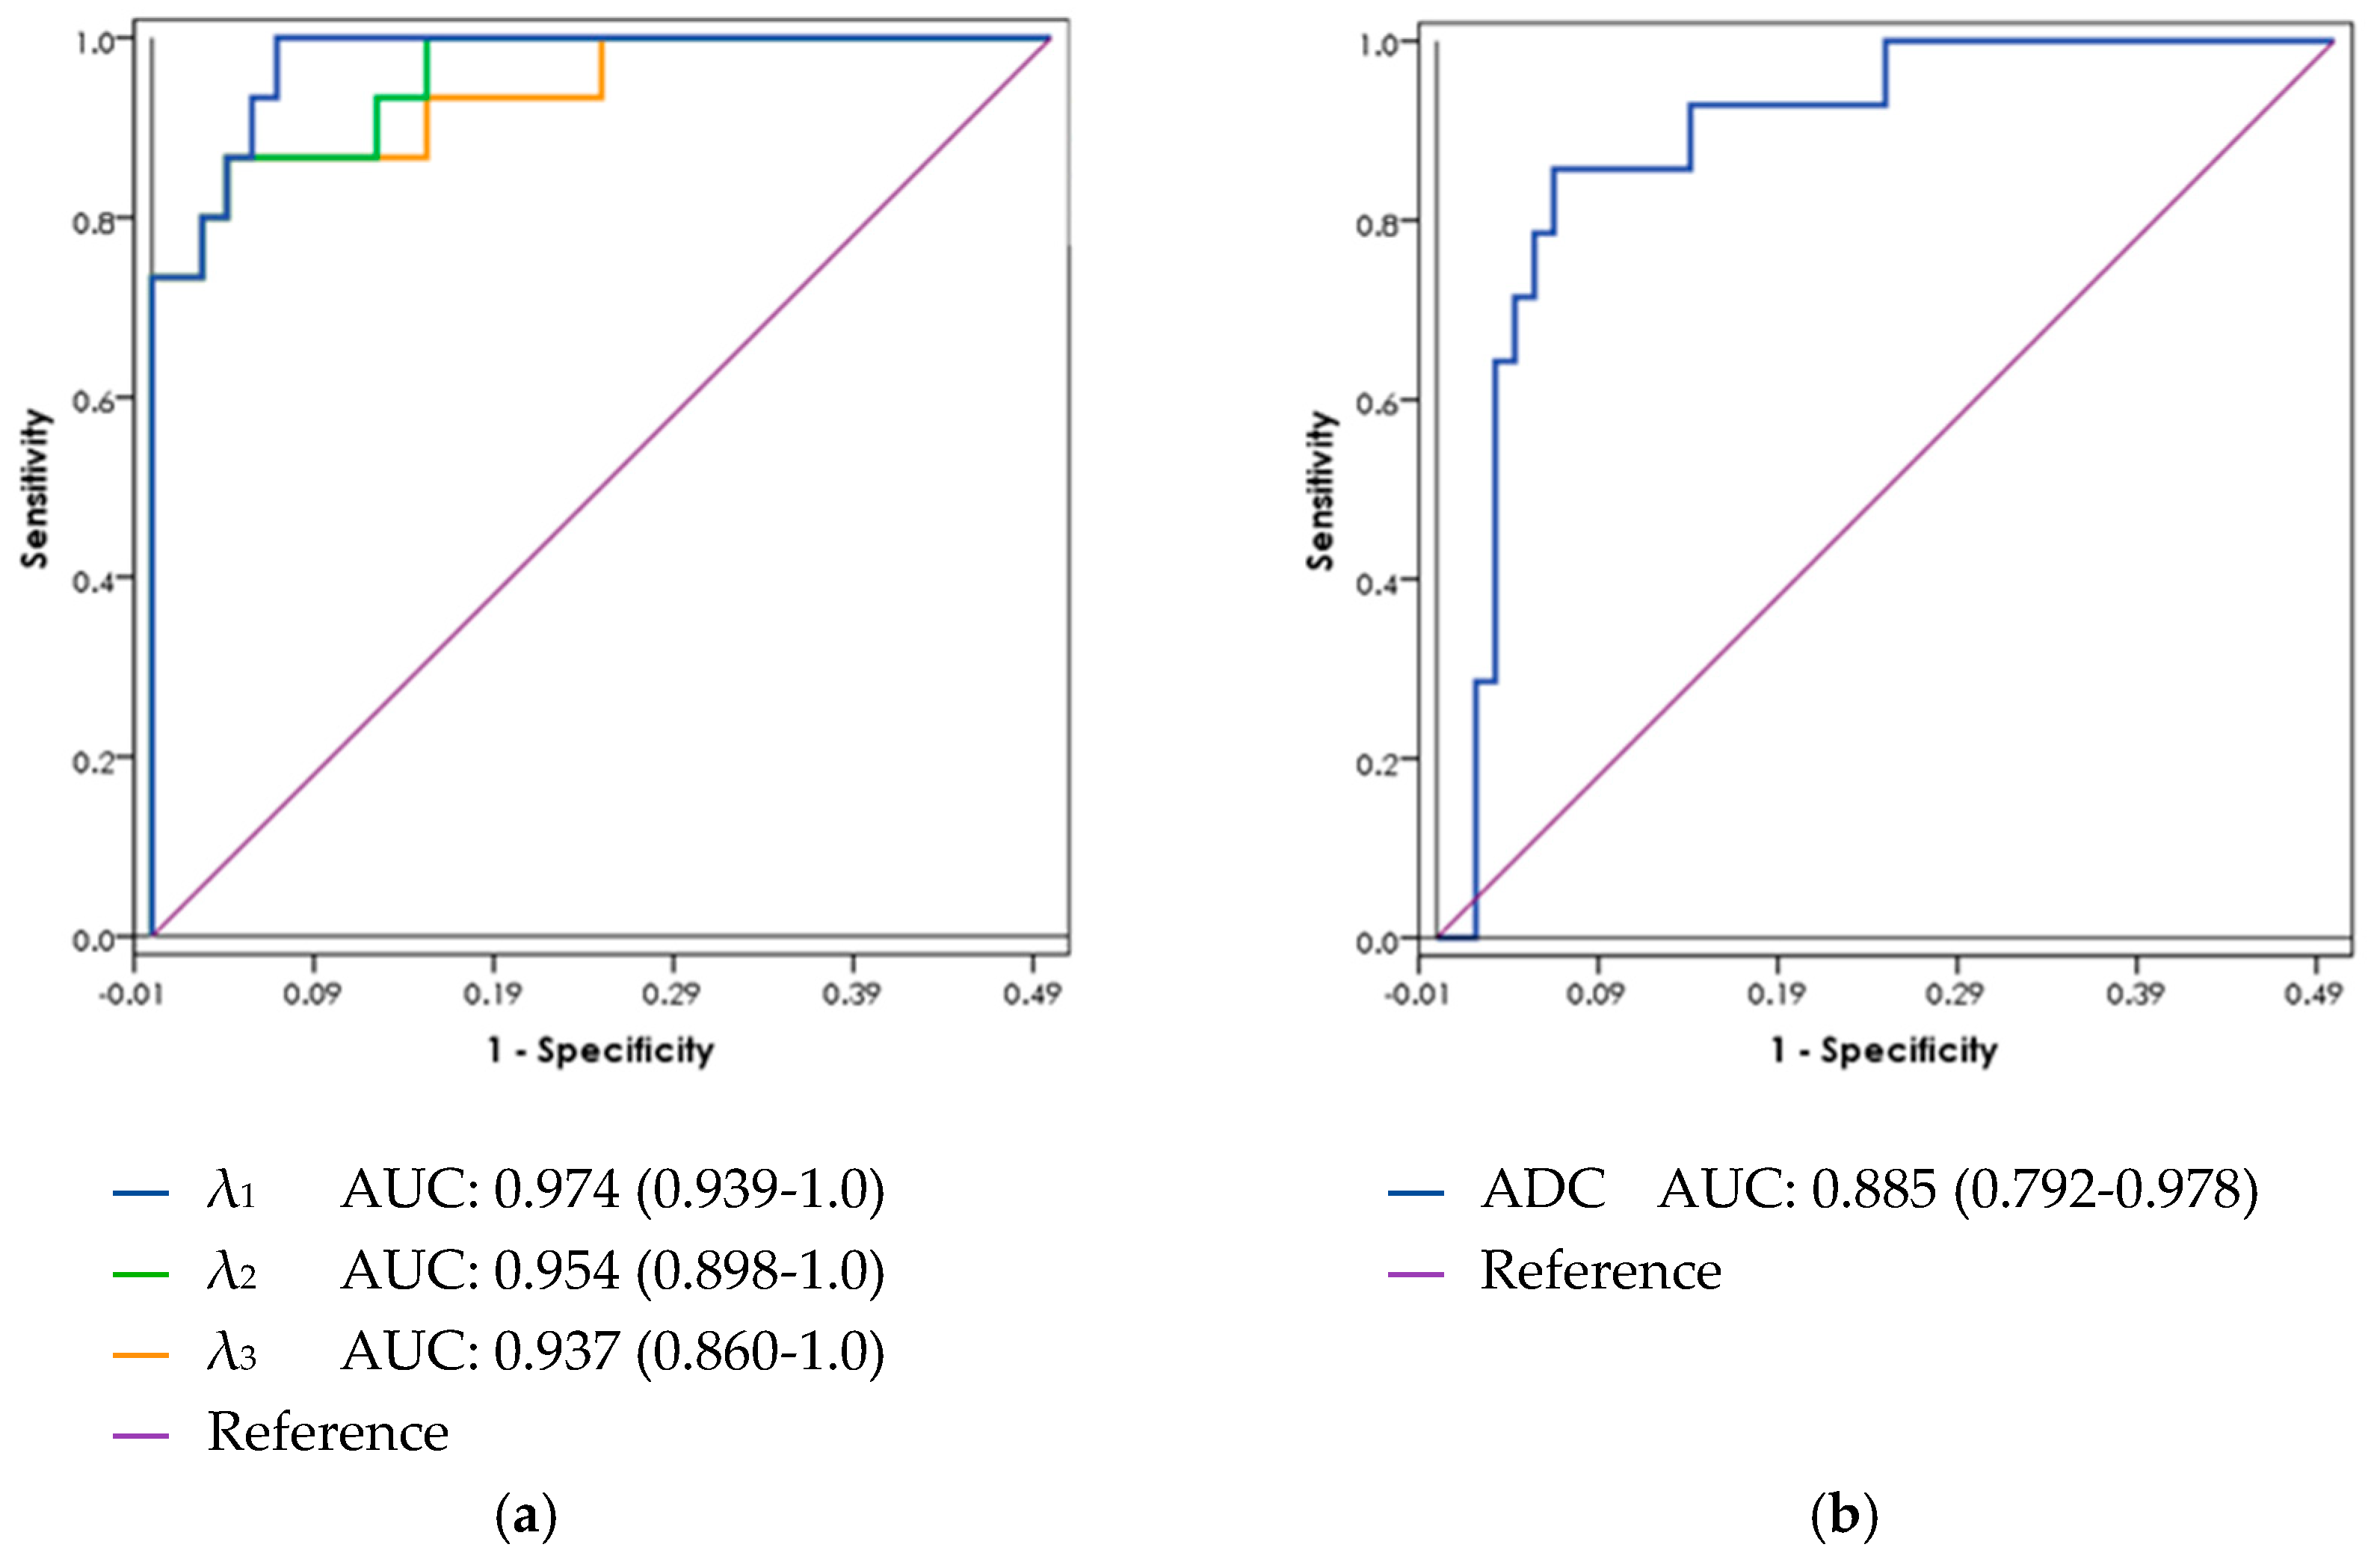

3.4. ROC Curve Analysis